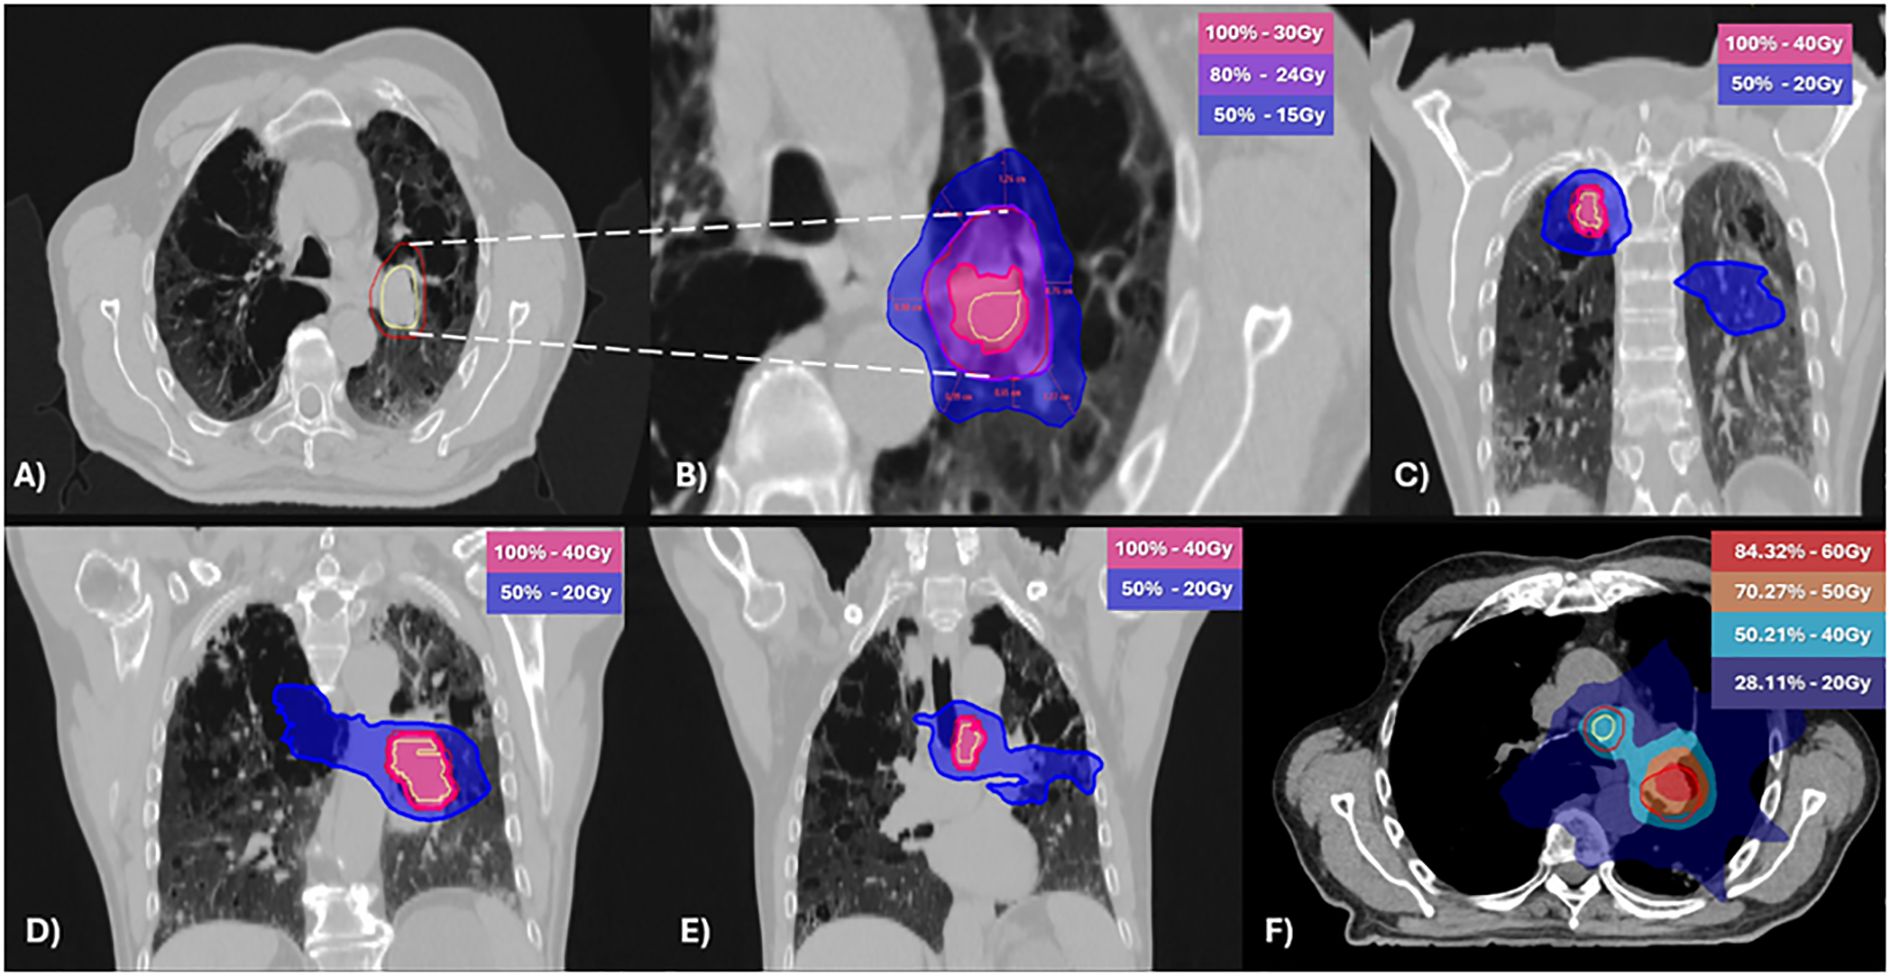

After a multidisciplinary discussion and respiratory function assessment (Table 1) it was decided to proceed with a new iRT treatment, but outside the context of SBRT. An equivalent dose in 2 Gy fractions (EQD2) with an alpha/beta of 10 (12) was used to reduce the risk of radiotoxicity, prescribing 40 Gy in 20 fractions to achieve volume coverage with VMAT technique, targeting the three sites of oligoprogression. The evaluation of the treatment plan was performed using rigid registration for dose accumulation (Figure 2) and biological summation; the data are presented in Table 2.

Figure 2. Stereotactic body radiotherapy [SBRT; (A, B)] and normo-fractionated radiotherapy (C-E) plans with geometrical dose accumulation (F). (A) Clinical target volume (CTV) in yellow and planning target volume (PTV) in red. (B) Dose at 2 cm from the PTV (D2cm) not exceeding 50% of the prescribed PTV dose. (C–E) Isodose distributions of the normo-fractionated radiotherapy plan (F) The accumulative dose of 60Gy and 50Gy was limited to the pretreated area. Light blue (40Gy) and blue (20Gy) correspond to regions treated with normo-fractionated radiotherapy.

The biological sum of both treatments in the re-irradiated lesion (station 11L) was EQD2: 76 Gy and biologically effective dose (BED): 91.2 Gy (12) with an adequate dose limitation to the organs at risk (OARs) (20), as showed in Table 2.